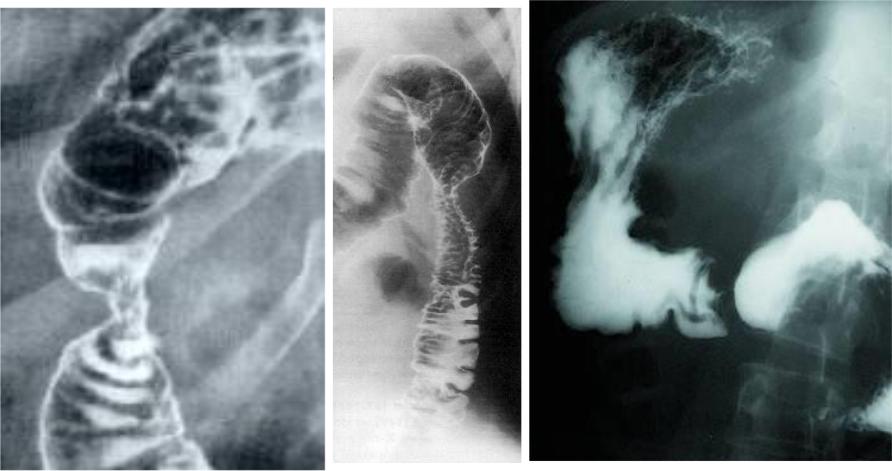

Рентгенография: стеноз двенадцатиперстной кишки при хроническом панкреатите: